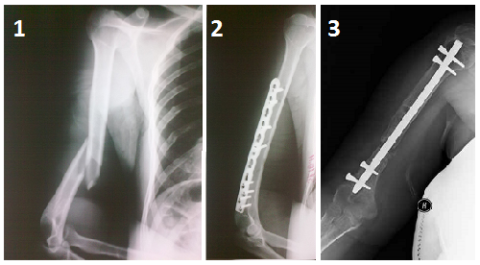

Медицинские снимки: Пластина в левом предплечье